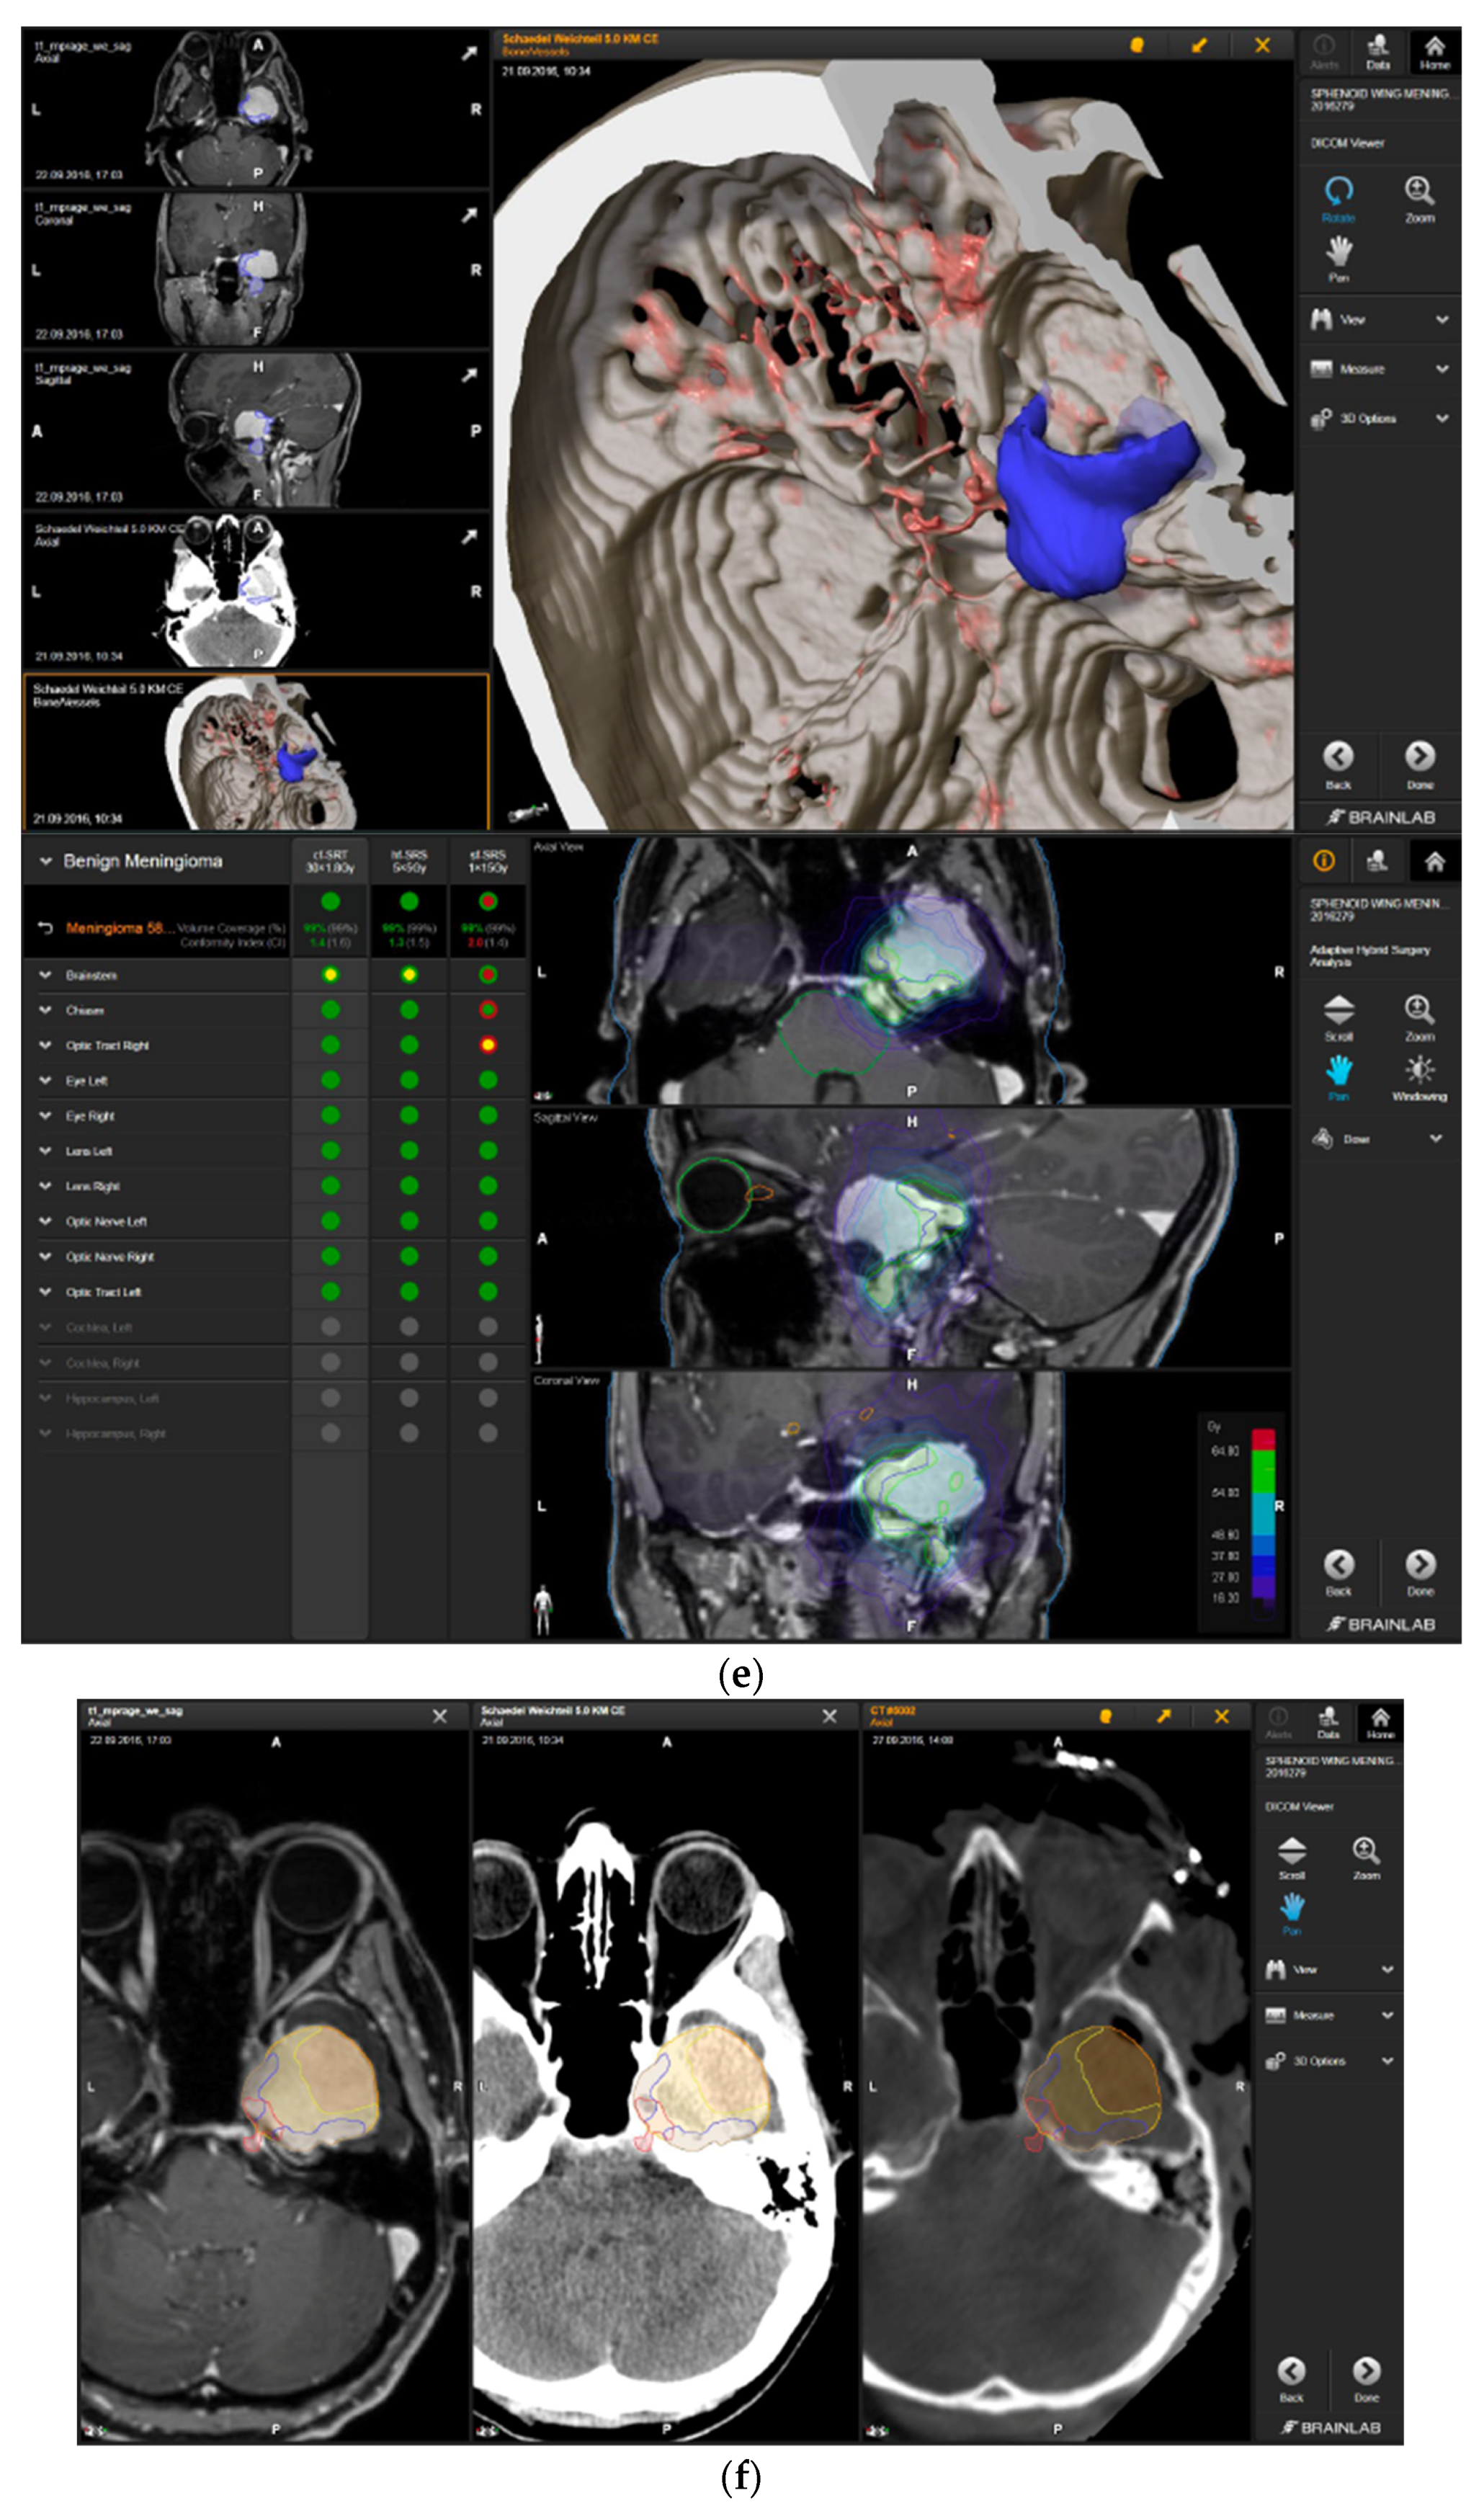

A 58-year-old female presented with progressive headache, difficulty swallowing, diplopia, hearing loss, and reduced face sensitivity on the right side (Figure 4). Elective craniotomy and AHSA-assisted tumor resection were performed. The patient underwent hypofractionated radiosurgery (5 × 5 Gy) of the residual meningioma one year after tumor resection.

Figure 4.

Second representative case of AHSA-supported tumor resection. (a) MRI imaging of petroclival meningioma (axial, coronal, sagittal). (b) Depiction of preoperative tumor volume (orange) and planned residual tumor volume (red). (c) AHSA summary table showing the stereotactic radiation constraints for the preoperatively planned residual tumor volume. With this plan, conventional fractionation and hypofractionation were feasible with effective tumor coverage.

—right hippocampus: mean dose unsafe, max. dose is marginally safe. (e) Second intraoperative ISU with residual tumor volume of 74% and calculated dose constraints for hypofractionated radiotherapy. Single dose stereotactic radiosurgery was still not considered feasible with this residual tumor volume. The dose constraints for organs at risk for conventional and hypofractionated radiotherapy were unchanged compared to the first ISU. (f) Third intraoperative ISU with residual tumor volume of 47% and calculated dose constraints for conventional, hypofractionated radiotherapy, and radiosurgery. The current dose constraints for organs at risk were the following for conventional radiation:

—right hippocampus: unsafe. (g) Overlay of preoperatively estimated and intraoperative effective residual tumor volume in AHSA. (h) Final intraoperative dose constraints after last ISU and data fusion with intraoperative CT. The dose constraints for OARs appeared to improve and were as follows for conventional and hypofractionated radiotherapy:

—brainstem: mean dose is safe, max. dose is marginally safe.

—brainstem: mean dose safe, max. dose unsafe;

—chiasm: mean dose unsafe, max. dose safe;

—right optic tract: mean dose unsafe, max. dose safe. (i) Comparison of pre- and 3 months postoperative MRI for stereotactic radiation planning. The residual tumor was finally treated with hypofractionated radiotherapy (5 × 5 Gy).